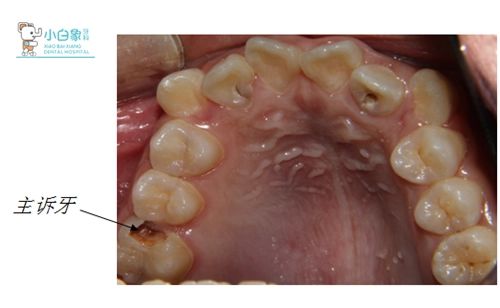

主诉:右上后牙疼痛10日余。

检查:颌面部查未见异常,口内查:牙列不齐,16近中临面龋坏达髓腔,近中缺损至龈下,探诊(-),温度测试无反应,叩(土),牙龈无红肿。36合面大面积缺损,髓腔暴漏,探诊(-),温度测试无反应,叩(+),牙龈无红肿。17,26,27,37,46,47合面龋坏达牙本质深层,探诊敏感,温度测试正常。14,24合面龋坏达牙本质浅层,探诊(-),温度测试正常。15,25,34,35,44,45萌出,窝沟较深,着色,无龋坏。12,22舌侧窝沟龋坏达牙本质深层,探诊敏感,温度测试正常。全口卫生差,软垢覆盖牙面二分之一,牙龈无红肿。

X线:16低密度影像达髓角

36根尖见低密度影像